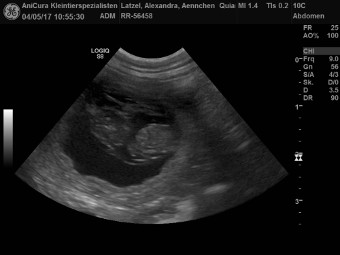

| 04.05.2017 |

| Quiana von Waltenweiler genannt Ännchen ist Schwanger! Hier seht ihr die Ultraschallbilder |